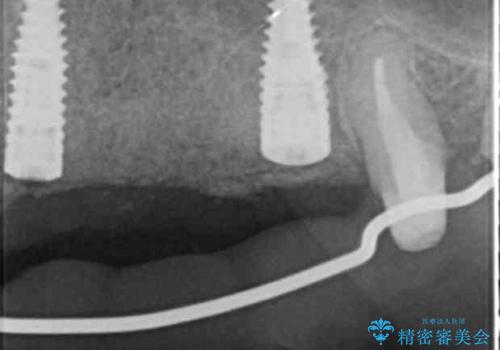

抜去を行ったのち、インプラント治療を計画しますが骨量が少ないため、まず骨の造成を行ったのちインプラントを埋入していく治療計画としました。